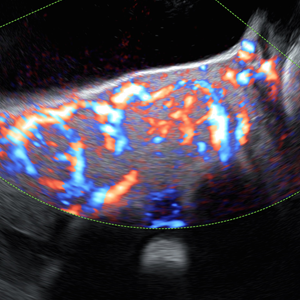

- Pionero en México en ofrecer diagnóstico por ultrasonido dentro del consultorio, así como en incorporar tecnología 3D y Doppler.